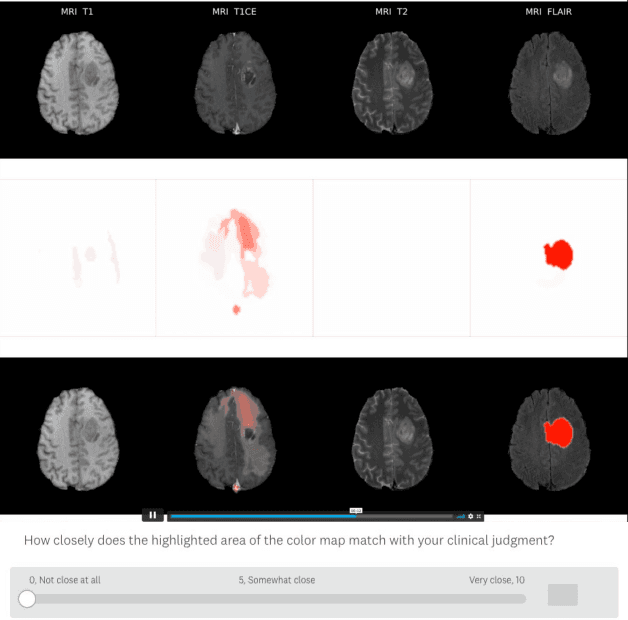

Abstract:Being able to explain the prediction to clinical end-users is a necessity to leverage the power of artificial intelligence (AI) models for clinical decision support. For medical images, a feature attribution map, or heatmap, is the most common form of explanation that highlights important features for AI models' prediction. However, it is unknown how well heatmaps perform on explaining decisions on multi-modal medical images, where each image modality or channel visualizes distinct clinical information of the same underlying biomedical phenomenon. Understanding such modality-dependent features is essential for clinical users' interpretation of AI decisions. To tackle this clinically important but technically ignored problem, we propose the modality-specific feature importance (MSFI) metric. It encodes clinical image and explanation interpretation patterns of modality prioritization and modality-specific feature localization. We conduct a clinical requirement-grounded, systematic evaluation using computational methods and a clinician user study. Results show that the examined 16 heatmap algorithms failed to fulfill clinical requirements to correctly indicate AI model decision process or decision quality. The evaluation and MSFI metric can guide the design and selection of XAI algorithms to meet clinical requirements on multi-modal explanation.

Abstract:Explainable artificial intelligence (XAI) is essential for enabling clinical users to get informed decision support from AI and comply with evidence-based medical practice. Applying XAI in clinical settings requires proper evaluation criteria to ensure the explanation technique is both technically sound and clinically useful, but specific support is lacking to achieve this goal. To bridge the research gap, we propose the Clinical XAI Guidelines that consist of five criteria a clinical XAI needs to be optimized for. The guidelines recommend choosing an explanation form based on Guideline 1 (G1) Understandability and G2 Clinical relevance. For the chosen explanation form, its specific XAI technique should be optimized for G3 Truthfulness, G4 Informative plausibility, and G5 Computational efficiency. Following the guidelines, we conducted a systematic evaluation on a novel problem of multi-modal medical image explanation with two clinical tasks, and proposed new evaluation metrics accordingly. The evaluated 16 commonly-used heatmap XAI techniques were not suitable for clinical use due to their failure in \textbf{G3} and \textbf{G4}. Our evaluation demonstrated the use of Clinical XAI Guidelines to support the design and evaluation for clinically viable XAI.

Abstract:Being able to explain the prediction to clinical end-users is a necessity to leverage the power of AI models for clinical decision support. For medical images, saliency maps are the most common form of explanation. The maps highlight important features for AI model's prediction. Although many saliency map methods have been proposed, it is unknown how well they perform on explaining decisions on multi-modal medical images, where each modality/channel carries distinct clinical meanings of the same underlying biomedical phenomenon. Understanding such modality-dependent features is essential for clinical users' interpretation of AI decisions. To tackle this clinically important but technically ignored problem, we propose the MSFI (Modality-Specific Feature Importance) metric to examine whether saliency maps can highlight modality-specific important features. MSFI encodes the clinical requirements on modality prioritization and modality-specific feature localization. Our evaluations on 16 commonly used saliency map methods, including a clinician user study, show that although most saliency map methods captured modality importance information in general, most of them failed to highlight modality-specific important features consistently and precisely. The evaluation results guide the choices of saliency map methods and provide insights to propose new ones targeting clinical applications.